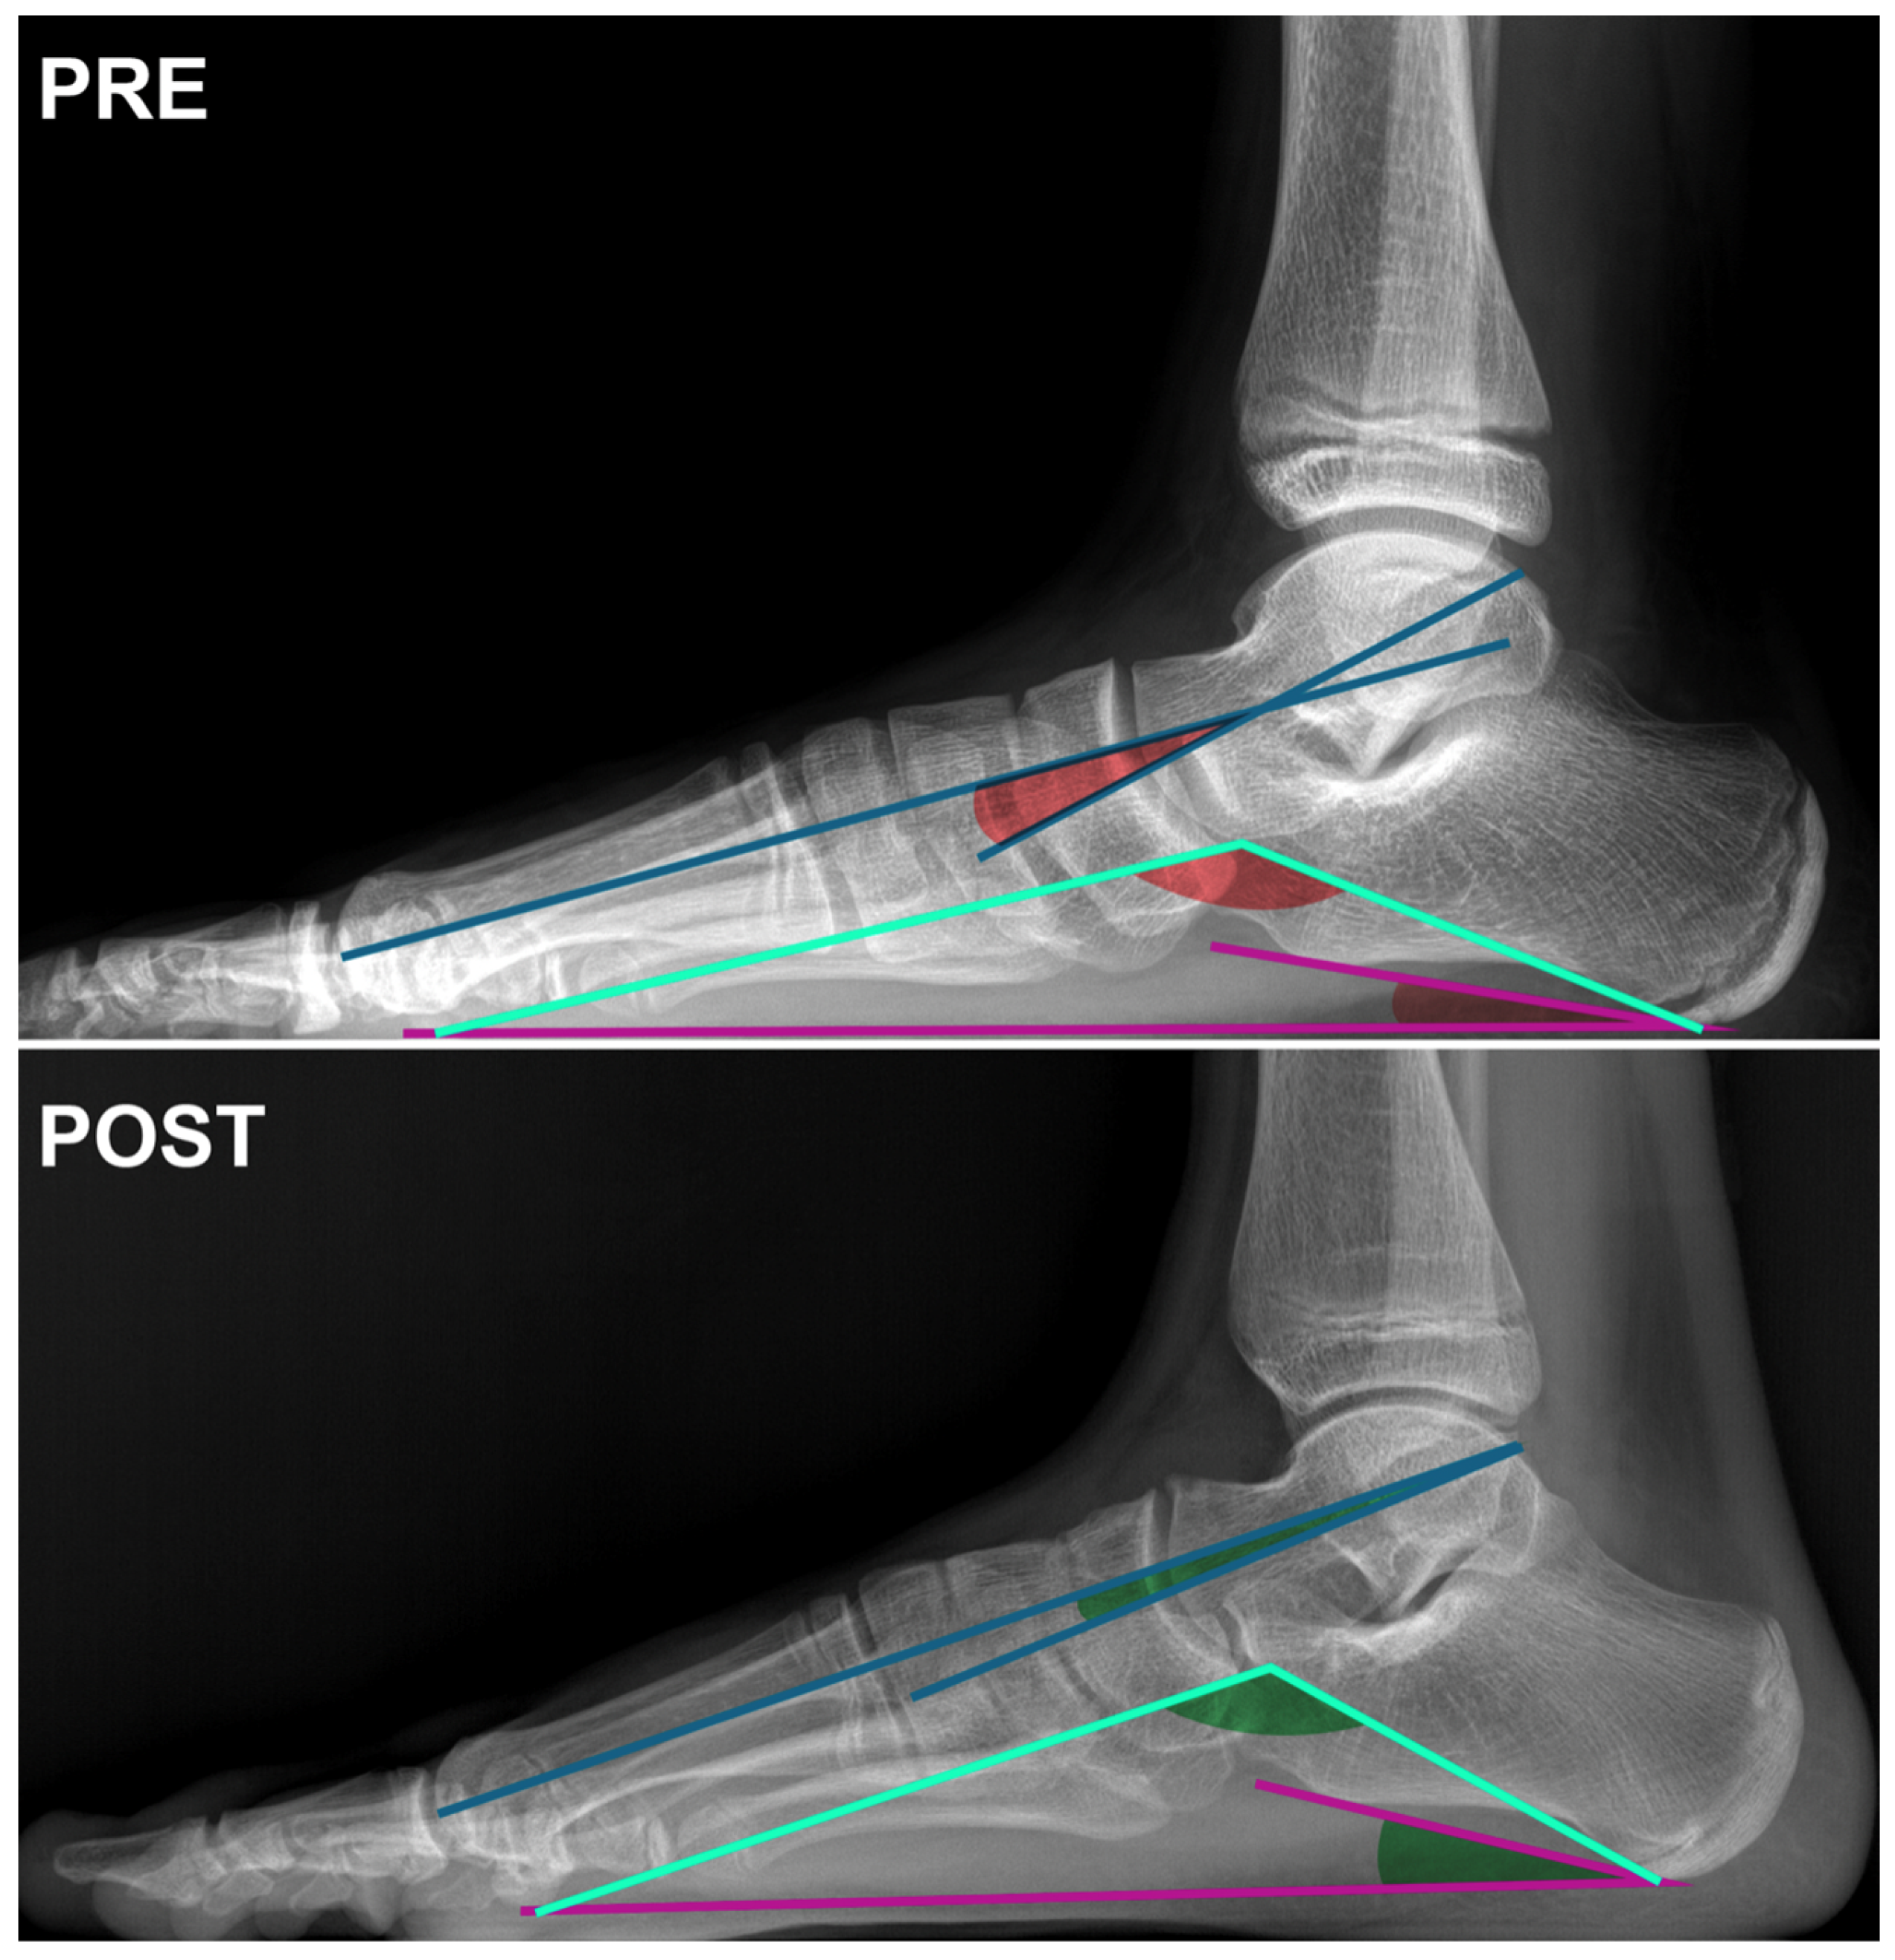

Regarding hindfoot-related angles, Meary, Costa Bartani, and Calcaneal Pitch showed an improvement but no significant difference was observed between the preoperative and postoperative measurements (Table 1 and Table 2, Figure 1 and Figure 2).

Figure 2. Lateral X-ray view of the foot of an 11-year-old female patient at the time of surgery (PRE) and at the 6-month postoperative follow-up (POST). Angle subtended by the blue lines: Meary’s angle; angle subtended by the cyan lines: Moreau-Bartani’s angle; angle subtended by the purple lines: Calcaneal Pitch angle.